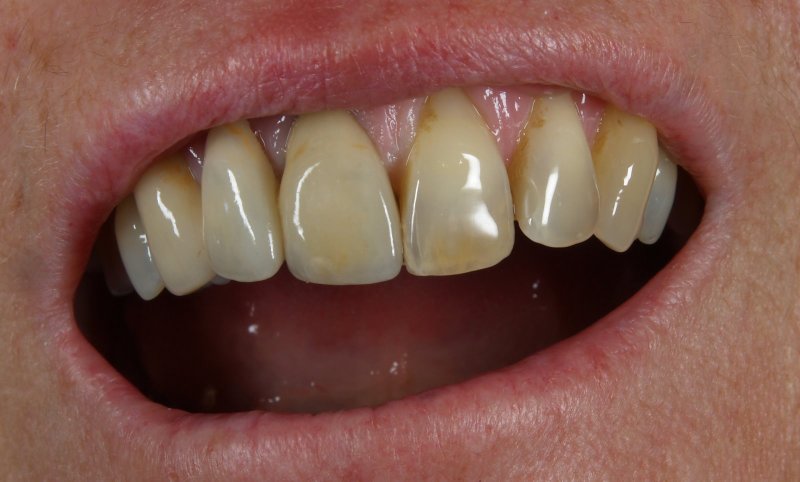

Patientenzufriedenheit

Vom Langzeitprovisorium zur TEK 1 Arbeit